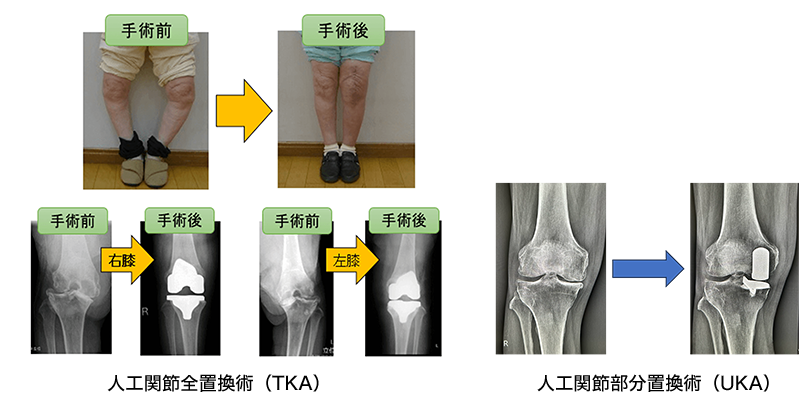

人工膝関節置換術(全置換、部分置換)

| 人工関節手術 | 人工膝関節置換術、人工股関節置換術など | 17例 | 51例 | 52例 | 35例 | 13例 |